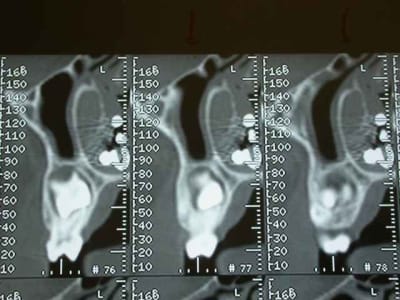

Je décide donc de faire réaliser un scanner et là c’est nouveau pour vous.

Une fois le scanner réalisé, je vois bien qu’il s’agit d’un objet composé de boules et l’adresse illico à son orl. Il la reçoit dans la foulée, et au vu du scanner, se refuse d’intervenir de peur de renvoyer plus loin l’objet. A son tour, il l’adresse à un hopital spécialisé enfants (Robert Debré). Au service ORL, ils tentent de retirer l’objet avec une pince (comme Dr House le faisait dans un épisode) et rien de neuf, aucune progression.